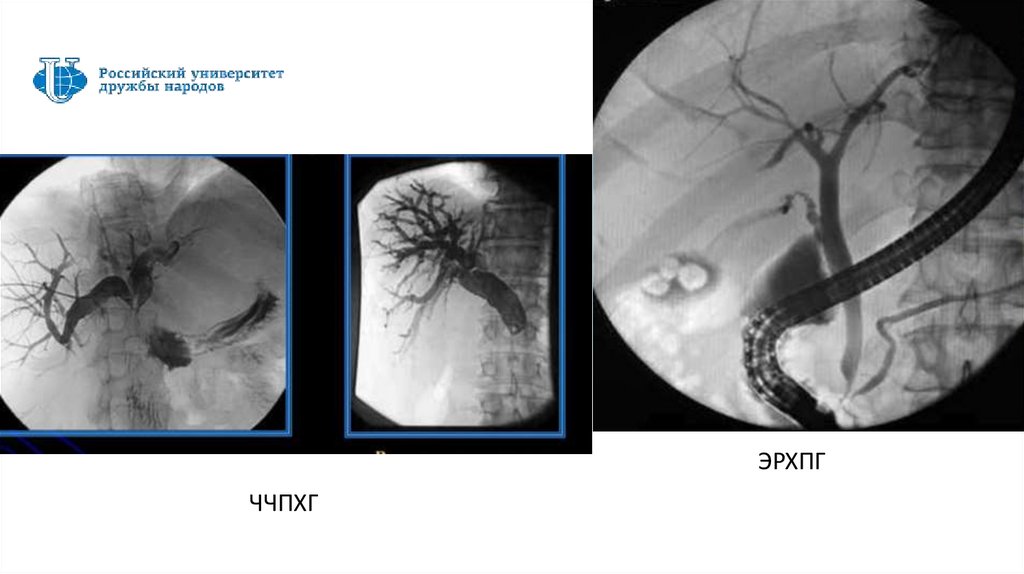

ЭРХПГ

ЧЧПХГ

брюшной полости

1. Эндоскопическая ретроградная

панкреатохолангиография – ЭРХПГ

2. Диагностическая лапароскопия